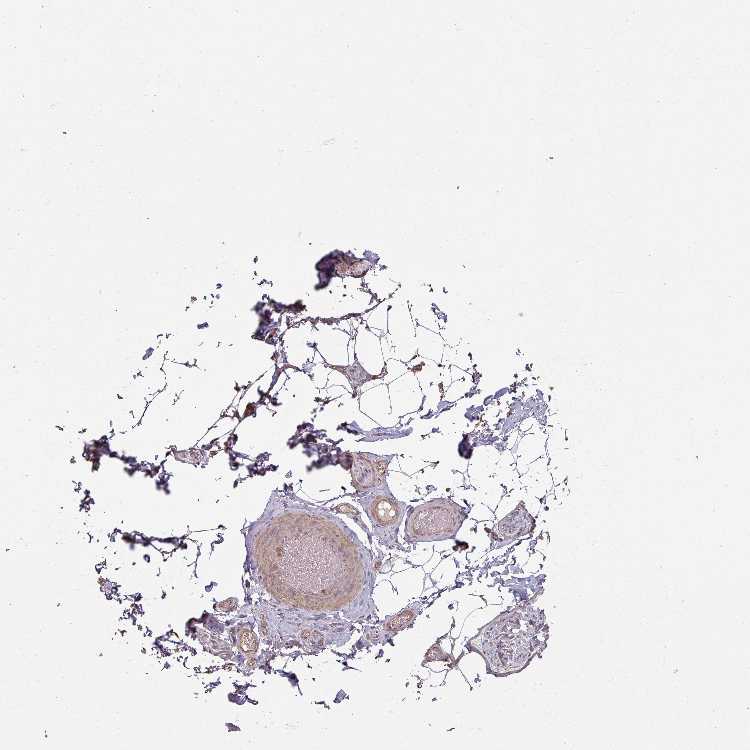

ADIPOSE TISSUE - Antibody stainingi

Antibody staining in the annotated cell types in the current human tissue is reported as not detected, low, medium, or high, based on conventional immunohistochemistry profiling in selected tissues. This score is based on the combination of the staining intensity and fraction of stained cells.

Each image is clickable and will lead to virtual microscopy that enables deeper exploration of all samples and also displays staining intensity scores, fraction scores and subcellular localization as well as patient and tissue information for each sample.

Antibody HPA040865Antibody HPA048197

Adipocytes LowNot detected